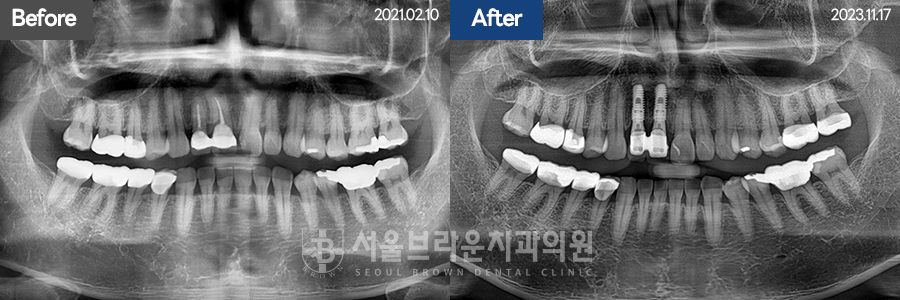

임플란트 | 30대 / 남 / 상악임플란트

30대 / 남 / 상악임플란트